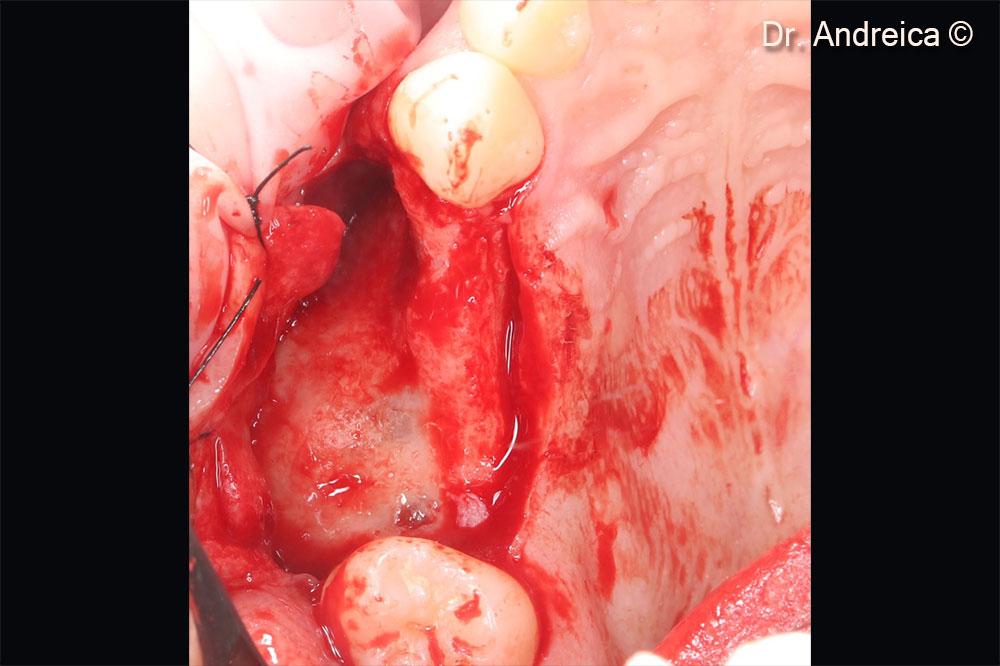

During membrane elevation a perforation occurred at the tip of the septa